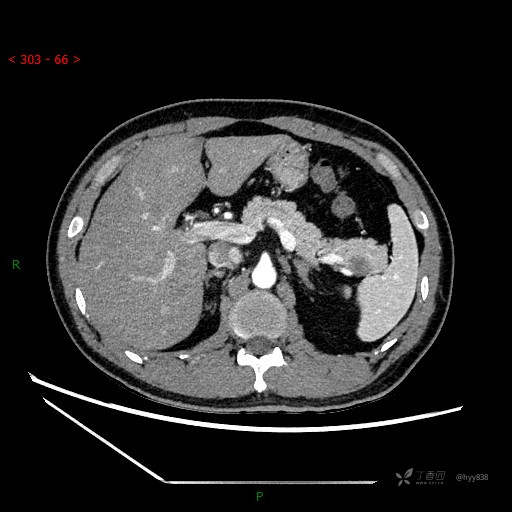

增强静脉期

CT值

42hu 48hu 57hu